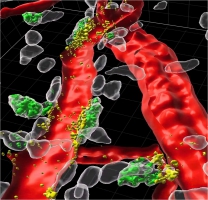

| Perivascular mast cells (white) are directly attached to blood vessels (red) in the mouse ear skin. Green mast cells represent those with access to the bloodstream that took up fluorescently-labeled avidin staining intracellular MC granules. Highlighted in yellow are those granules that are degranulated directionally within the blood vessel lumen. | The image depicts perivascular mast cells in mouse ear skin. White mast cells represent those directly attached to arterioles (red), ochre mast cells are associated with venules (blue). Blood vessel differentiation is based on staining the vessel marker endomucin. |

But how is the TNF of tissue-resident mast cells delivered to neutrophils circulating inside blood vessels? The Magdeburg scientists employed high-resolution 2-Photon-Microscopy to show in fascinating pictures that the mast cells use a surprising trick. They position themselves, guardian-like, directly around the blood vessel and even insert protrusions into the vessel lumen. In case of emergency, granula containing TNF are released directionally from these protrusions. Thereby the TNF immediately is present where the neutrophils can “see” it – in the bloodstream, circulating through the vessels. The TNF activates surface proteins on the neutrophils. Thereby the cells become stickier, can attach themselves at the vessel wall and then migrate into the surrounding tissue.

Prof. Dr. Anne Dudeck explains the significance of these results: “The capacity of mast cells to degranulate directionally into the blood stream might explain, why local allergen encounter can trigger a systemic anaphylactic shock. Next, we want to understand the exact mechanisms mast cells use to insert these protrusions into the vessel wall. Targeting these might reveal therapeutic strategies to dampen allergic shock or cytokine storm syndromes. At the same time, it might also enable us to harness the ability of mast cells to stimulate the immune response, notably the recruitment of neutrophils, during infections.”